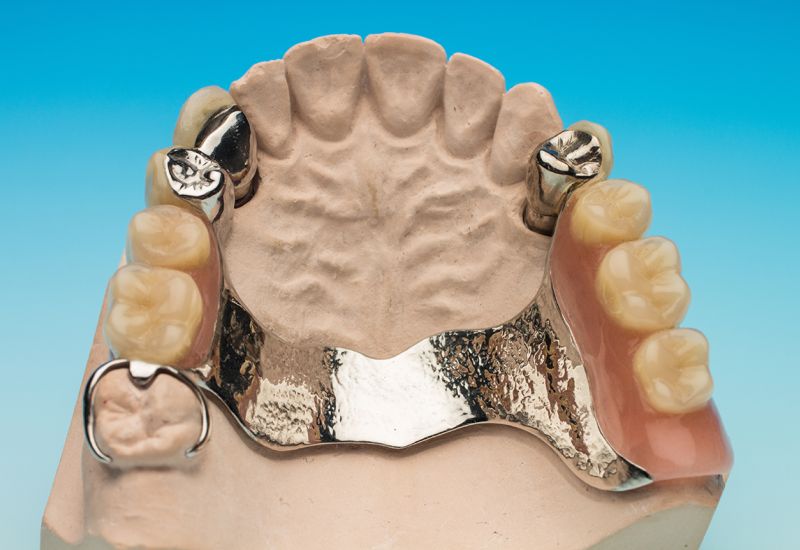

Modellgußtechnik

Sind mehrere Zähne verloren gegangen, befürworten die gesetzlichen Krankenkassen eine Klammerprothese. Diese Lösung birgt jedoch Nachteile. Durch die sichtbaren Klammern wird die Ästhetik beeinträchtigt. Unter anderem können auch Zahnfleischprobleme entstehen und die gesunden Zähne schädigen.

Hierfür bietet Ihnen ihr Dental-Labor Birgit Lorenz GmbH einen kombinierten Zahnersatz an.

Es handelt sich um einen festsitzenden Zahnersatz, der zugleich herausnehmbar ist. Um die Stabilität zu gewährleisten, werden gesunde Zähne mit einer festsitzenden Krone versehen, in denen hochpräzise und feinmechanische Verbindungselemente eingearbeitet sind.